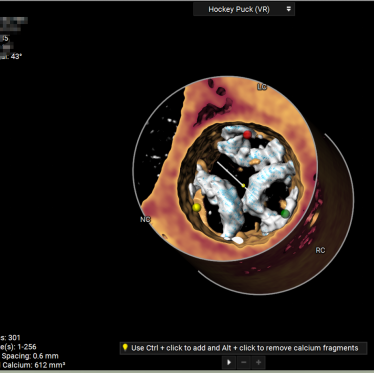

术前CT分析

主动脉根部测量

Annulus 20.7mm

LVOT 21.3mm

钙化积分 612

SOV

27.9*26.8*27.1mm

STJ 22.6mm

AAO 28.8mm

-

三叶瓣

流出道直筒型

重度钙化

STJ及升主无明显扩张